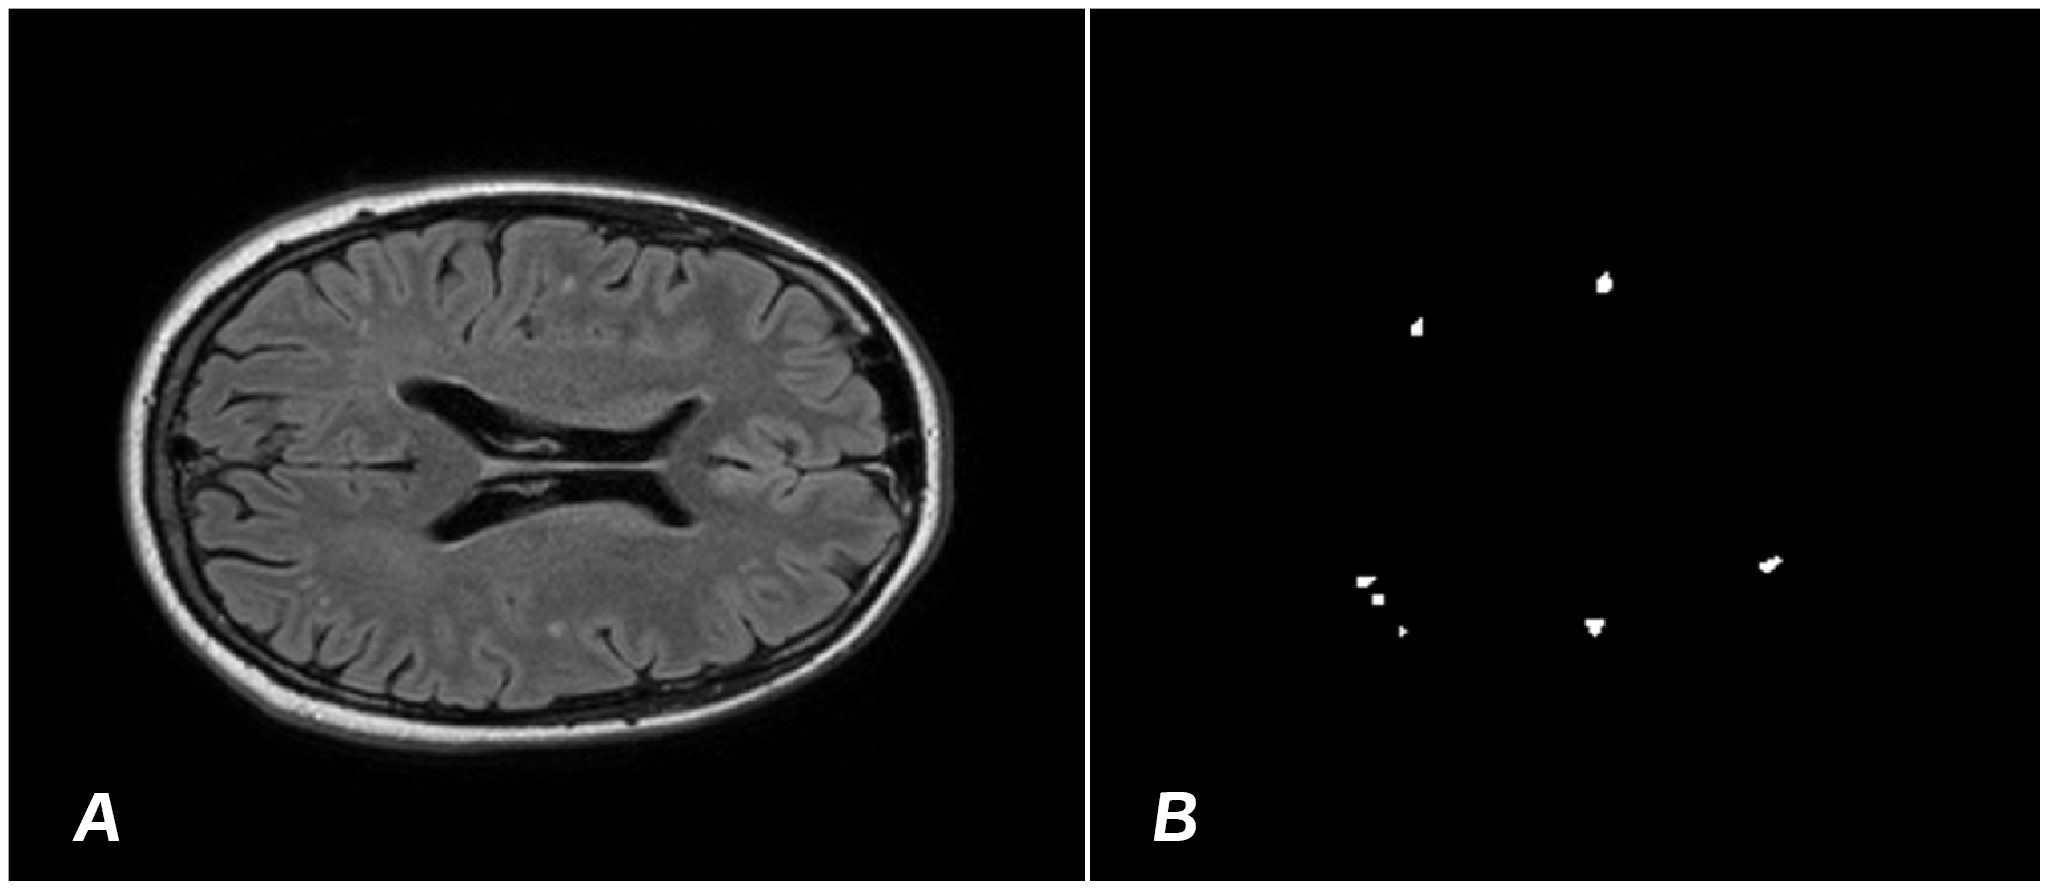

To train the model, images sized 512×512 pixels were used. The training was performed using stochastic gradient descent with a momentum of 0.9 and an initial learning rate of 0.001. The dataset was divided into training and testing samples in a 90/30 ratio. Following the segmentation of demyelination foci by the radiologist, images were obtained (Fig. 1) on the basis of which ‘masks’ were formed to train the YOLOv8 algorithm.

Figure 1. A – MRI T2 mode with a focus of demyelination. B – “mask” of demyelination foci obtained as a result of segmentation by a radiologist.